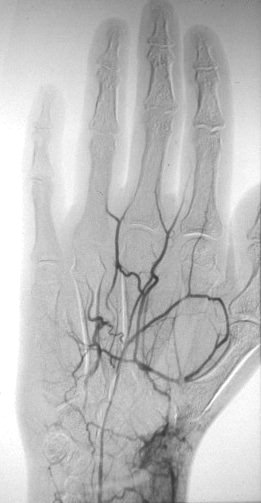

Case 2: more severe problem: ulnar artery is occluded as well. This patient signed out of the ICU AMA to have a smoke (5 pack a day - yeeow!)

Click for larger image

Case 2: The problem with revascularisation at this location is that the distal point of occlusion is at a branch - usually at a fork between the thumb and the palmar arch. Ideally, a distally branching reversed vein graft can supply both points, as was done here (vein graft, dorsal approach to first web space, distal left, thumb superior).